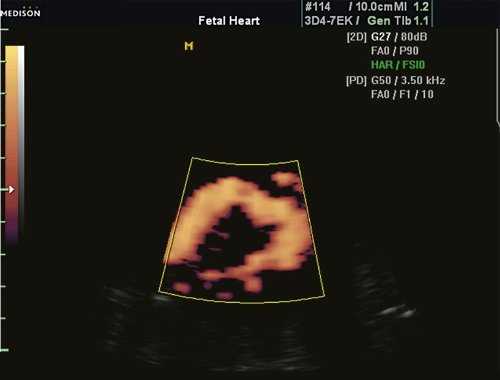

При эхокардиографии изучались четырехкамерный срез сердца плода (рис. 1) и срез через три сосуда (рис. 2). УЗИ проводилось трансабдоминальным датчиком, лишь при необходимости (затрудненная визуализация) использовался внутриполостной датчик. Четырехкамерный срез сердца плода при ультразвуковом сканировании трансабдоминальным датчиком визуализировался в 85% случаев, срез через сосуды - в 73%, при использовании трансвагинального датчика эти цифры существенно возрастали до 100 и 91% соответственно. Оптимизация пренатальной диагностики ВПС может быть достигнута путем строгого соблюдения основных методических правил. При оценке четырехкамерного среза плода необходимо оценить нормальное расположение сердца плода, исключив его эктопию (рис. 3), положение оси сердца плода, что не представляет никаких трудностей, нормальные пропорции и размеры камер сердца, движение створок атриовентрикулярных клапанов должно быть свободным, септальная створка трикуспидального клапана должна располагаться ближе к верхушке сердца (рис. 4). При оценке среза через три сосуда необходимо оценить взаиморасположение сосудов и их диаметр.

Рис. 1. Беременность 12 недель. Четырехкамерный срез сердца плода. Отчетливо видны камеры сердца.